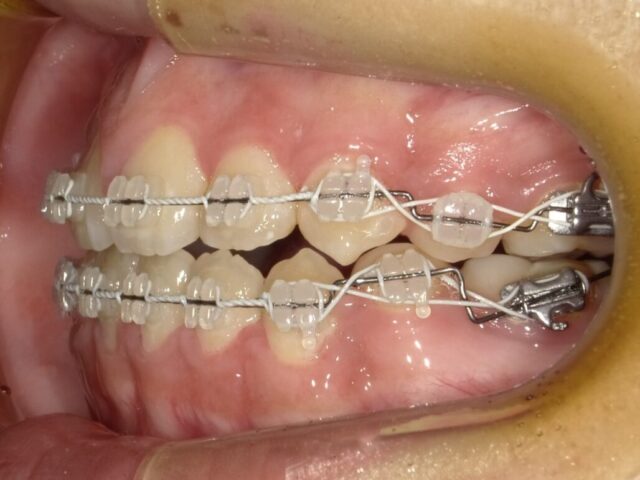

≪左側面観≫

2023年5月

2023年6月

2023年7月

2023年8月

2023年9月

2023年10月

2023年11月

2023年12月

2024年1月

2024年2月

2024年3月

2024年4月

2024年5月

2024年6月

2024年7月

2024年8月

2024年9月

2024年10月

2024年12月

2025年1月